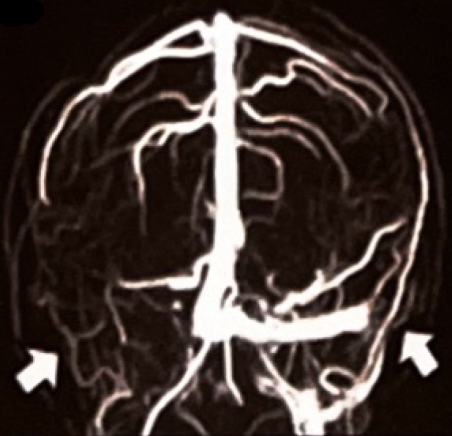

海证资本*仅供医学专业人士阅读参考华融资产 令医生“头痛”的头痛! 撰文|凌 白骆驼 偏头痛时常困扰青年女性,但今天这位患者头痛、发热反复发作,抗感染治疗效果欠佳,患者....